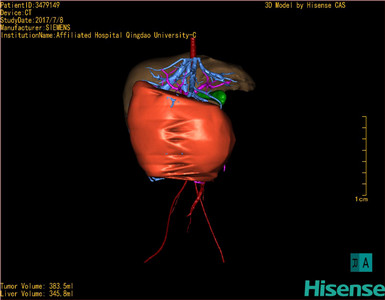

将0.625mm双源薄层CT资料的静脉期和动脉期Dicom格式文件导入海信CAS系统。

通过调节窗宽窗位调整CT序号,对肝实质,胆囊,下腔静脉,肿瘤,肝动脉、门静脉及肝静脉等进行三维重建;系统自动计算肝脏体积。

模拟手术操作,自动计算切除肿瘤体积。肝脏体积为345.8ml,肿瘤体积383.5ml,是肝脏体积的1.1倍,通过比对6-9月岁正常肝脏体积为257.75±51.05ml,通过术前模拟手术,精准判断切除后剩余肝脏体积能耐受,避免肝衰竭发生。

术前三维重建:

重建图片